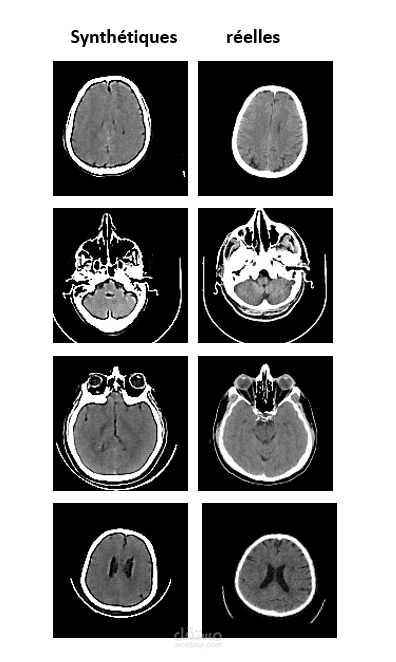

تطوير نموذج cVAE لتوليد صور أشعة مقطعية صناعية للسكتة الدماغية. الهدف هو موازنة البيانات وتحسين أداء نماذج التصنيف الطبية.